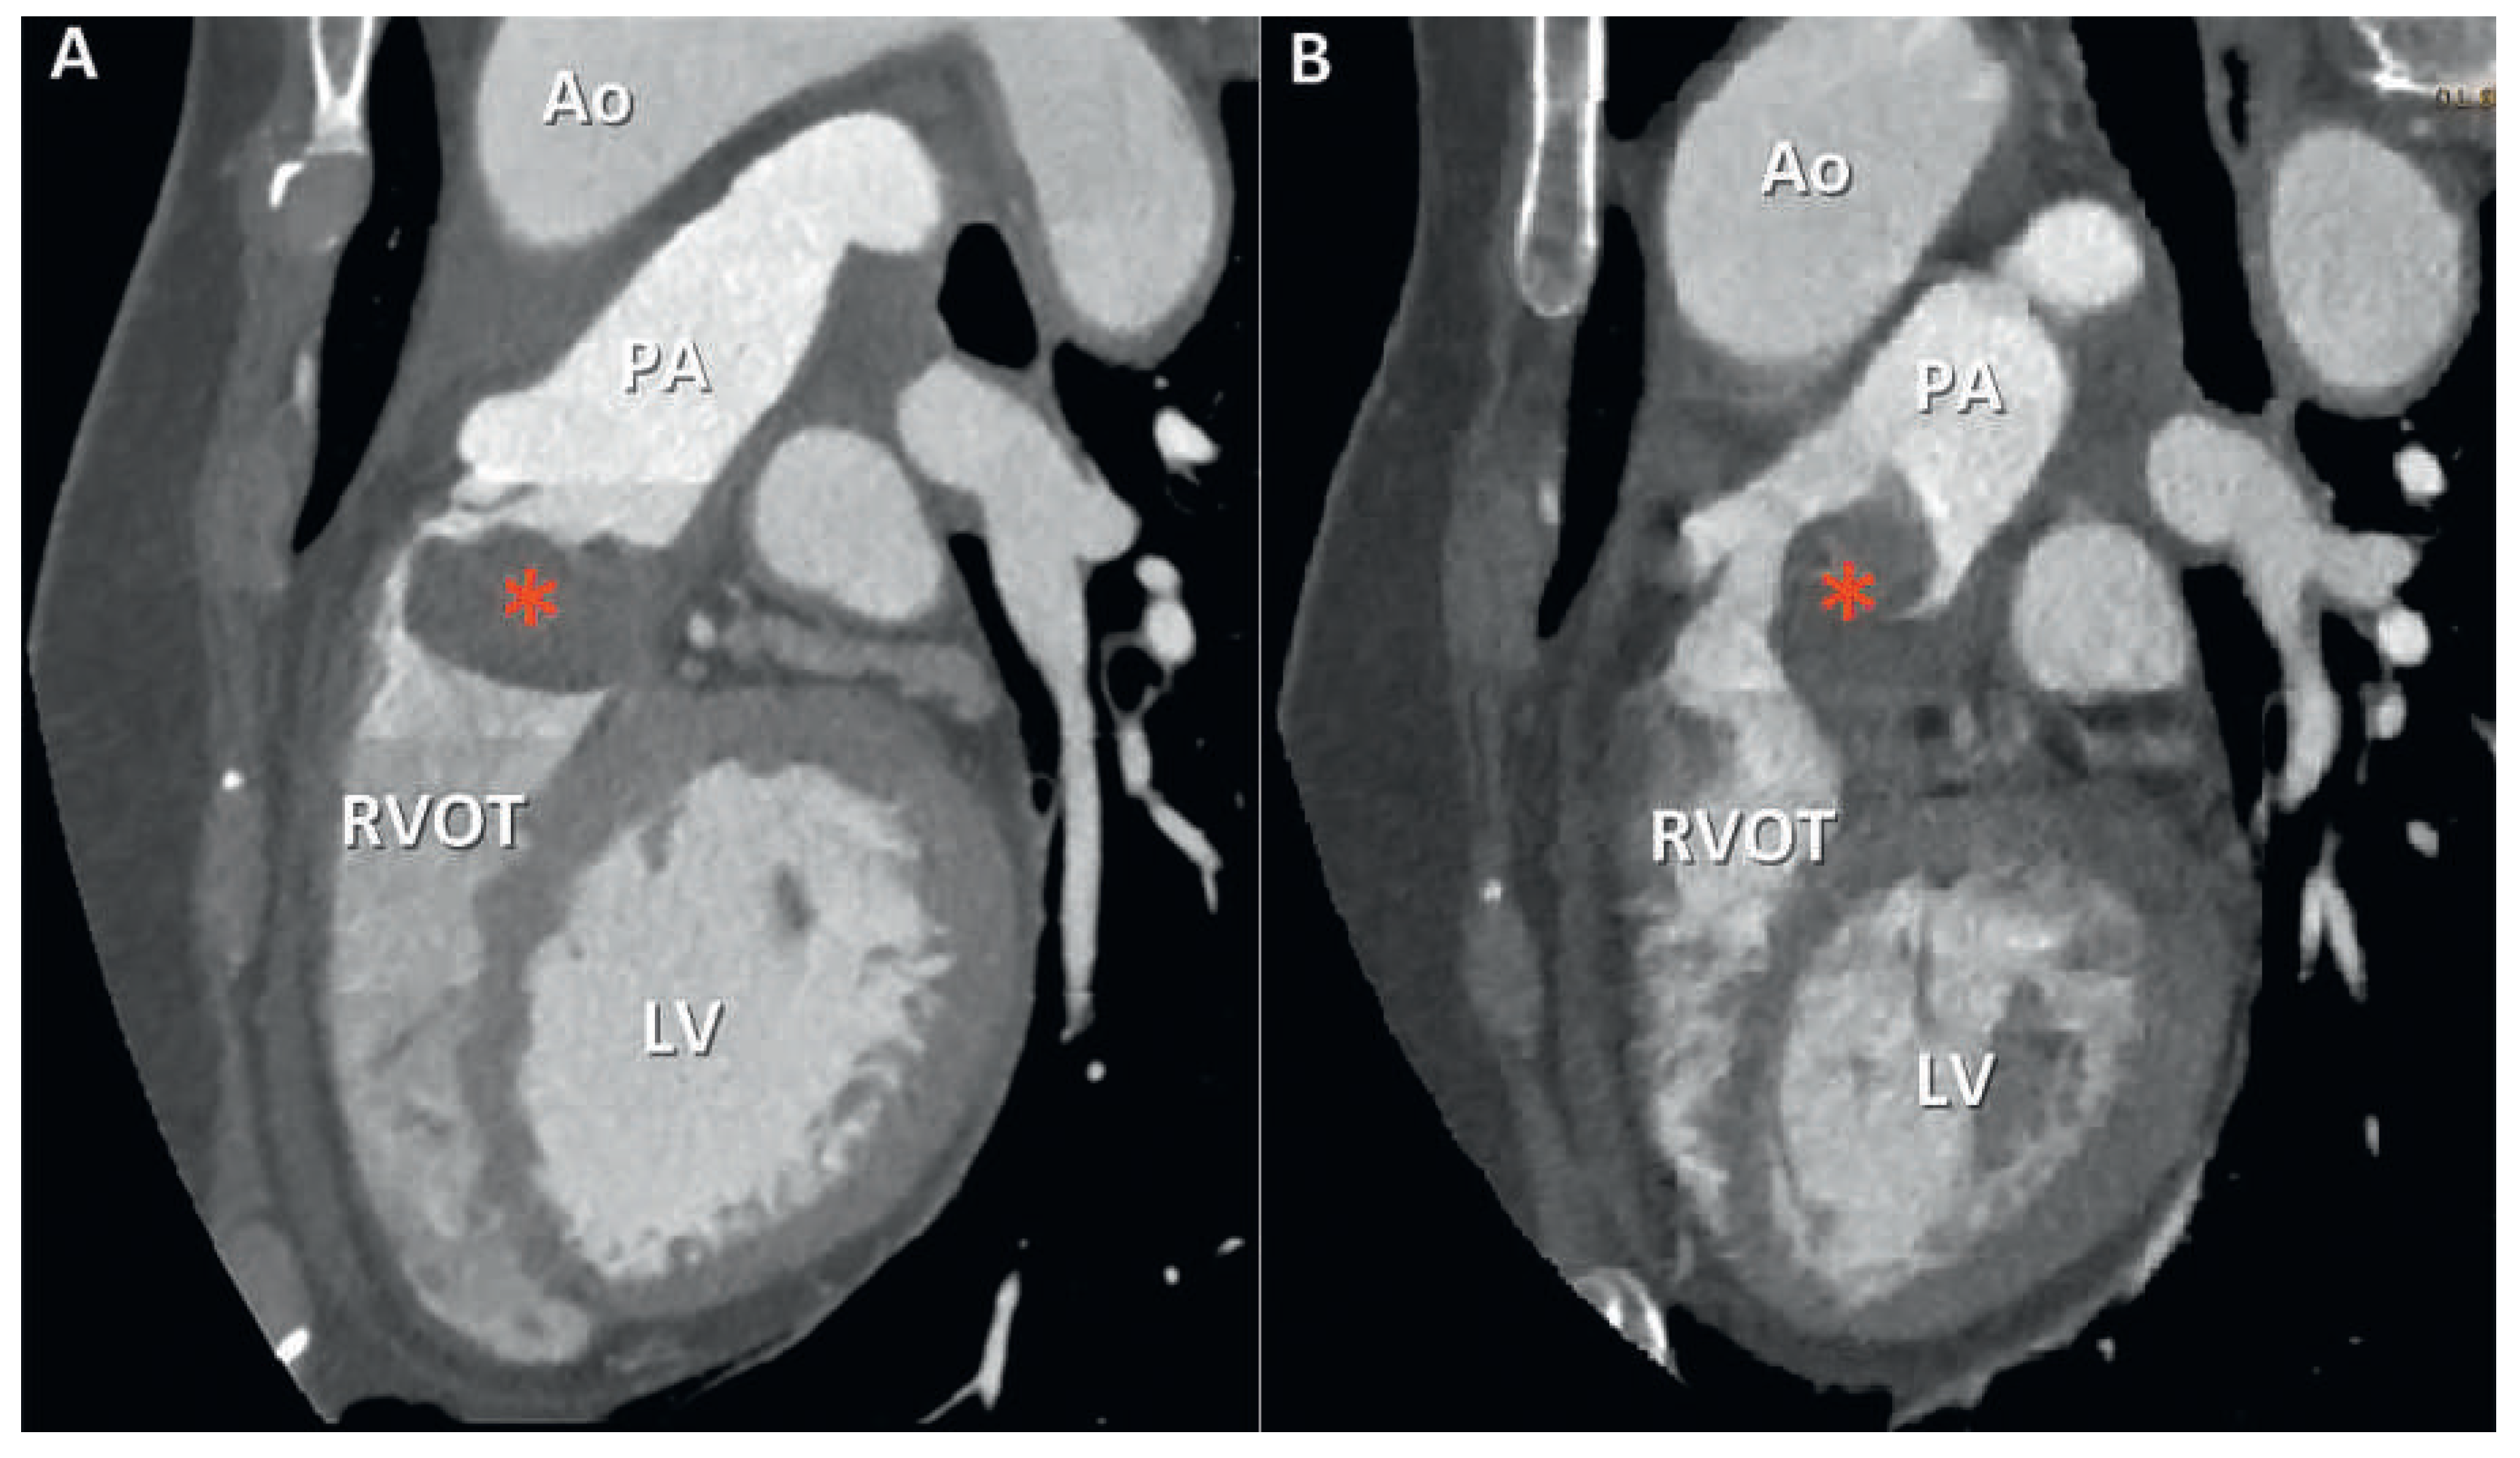

The patient was promptly referred to our institution where cardiac computed tomography (CT) revealed a 25 × 35 × 24 mm mass attached to the RVOT and extending into the pulmonary trunk through the pulmonary valve (Figure 2). After intravenous injection of 60–80 ml iodinated contrast material, late image acquisition showed inhomogeneous enhancement of the mass and mural enhancement of the pulmonary trunk suggestive of infiltration. This technique in the context of cardiac CT consists of acquiring images 60 seconds after CT angiography in order to optimise tissue enhancement. Fludeoxyglucose (18F) positron emission tomography-CT (18F-FDG PET-CT) revealed mild metabolic activity of the mass, with no signs of metastasis (Figure 3). Finally, cardiac magnetic resonance imaging (MRI) confirmed proximal extension of the valve mass, 4 cm towards the pulmonary trunk, without apparent invasion of the bifurcation (Figure 4). A hyperintense signal in T2-weighted images indicated oedema, whereas moderate signal-enhancement during resting perfusion suggested rich vascularisation. Intense signals on gadolinium enhancement sequences suggested rich extracellular content (fibrosis or extracellular matrix), but no significant necrosis (Figure 5).

Figure 2. Cardiac computed tomography, 2d multi-planar reformation showing the voluminous mass (*) attached to the pulmonary valve (A) and protruding in the pulmonary trunk during systole (B). Ao = aorta; LV = left ventricle; PA = pulmonary artery; RVOT = right ventricle outflow tract.